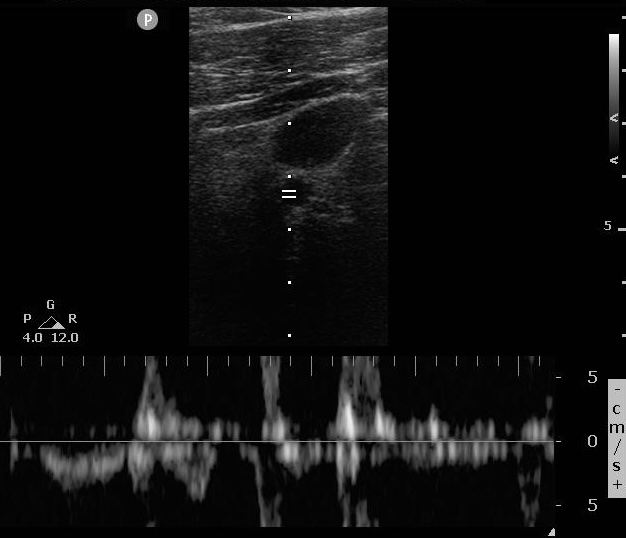

Case 1, Image 1.

Pulse wave Doppler started during ongoing compressions (with high amplitude tracings that alias). Image courtesy of Yale School of Medicine, Emergency Department.